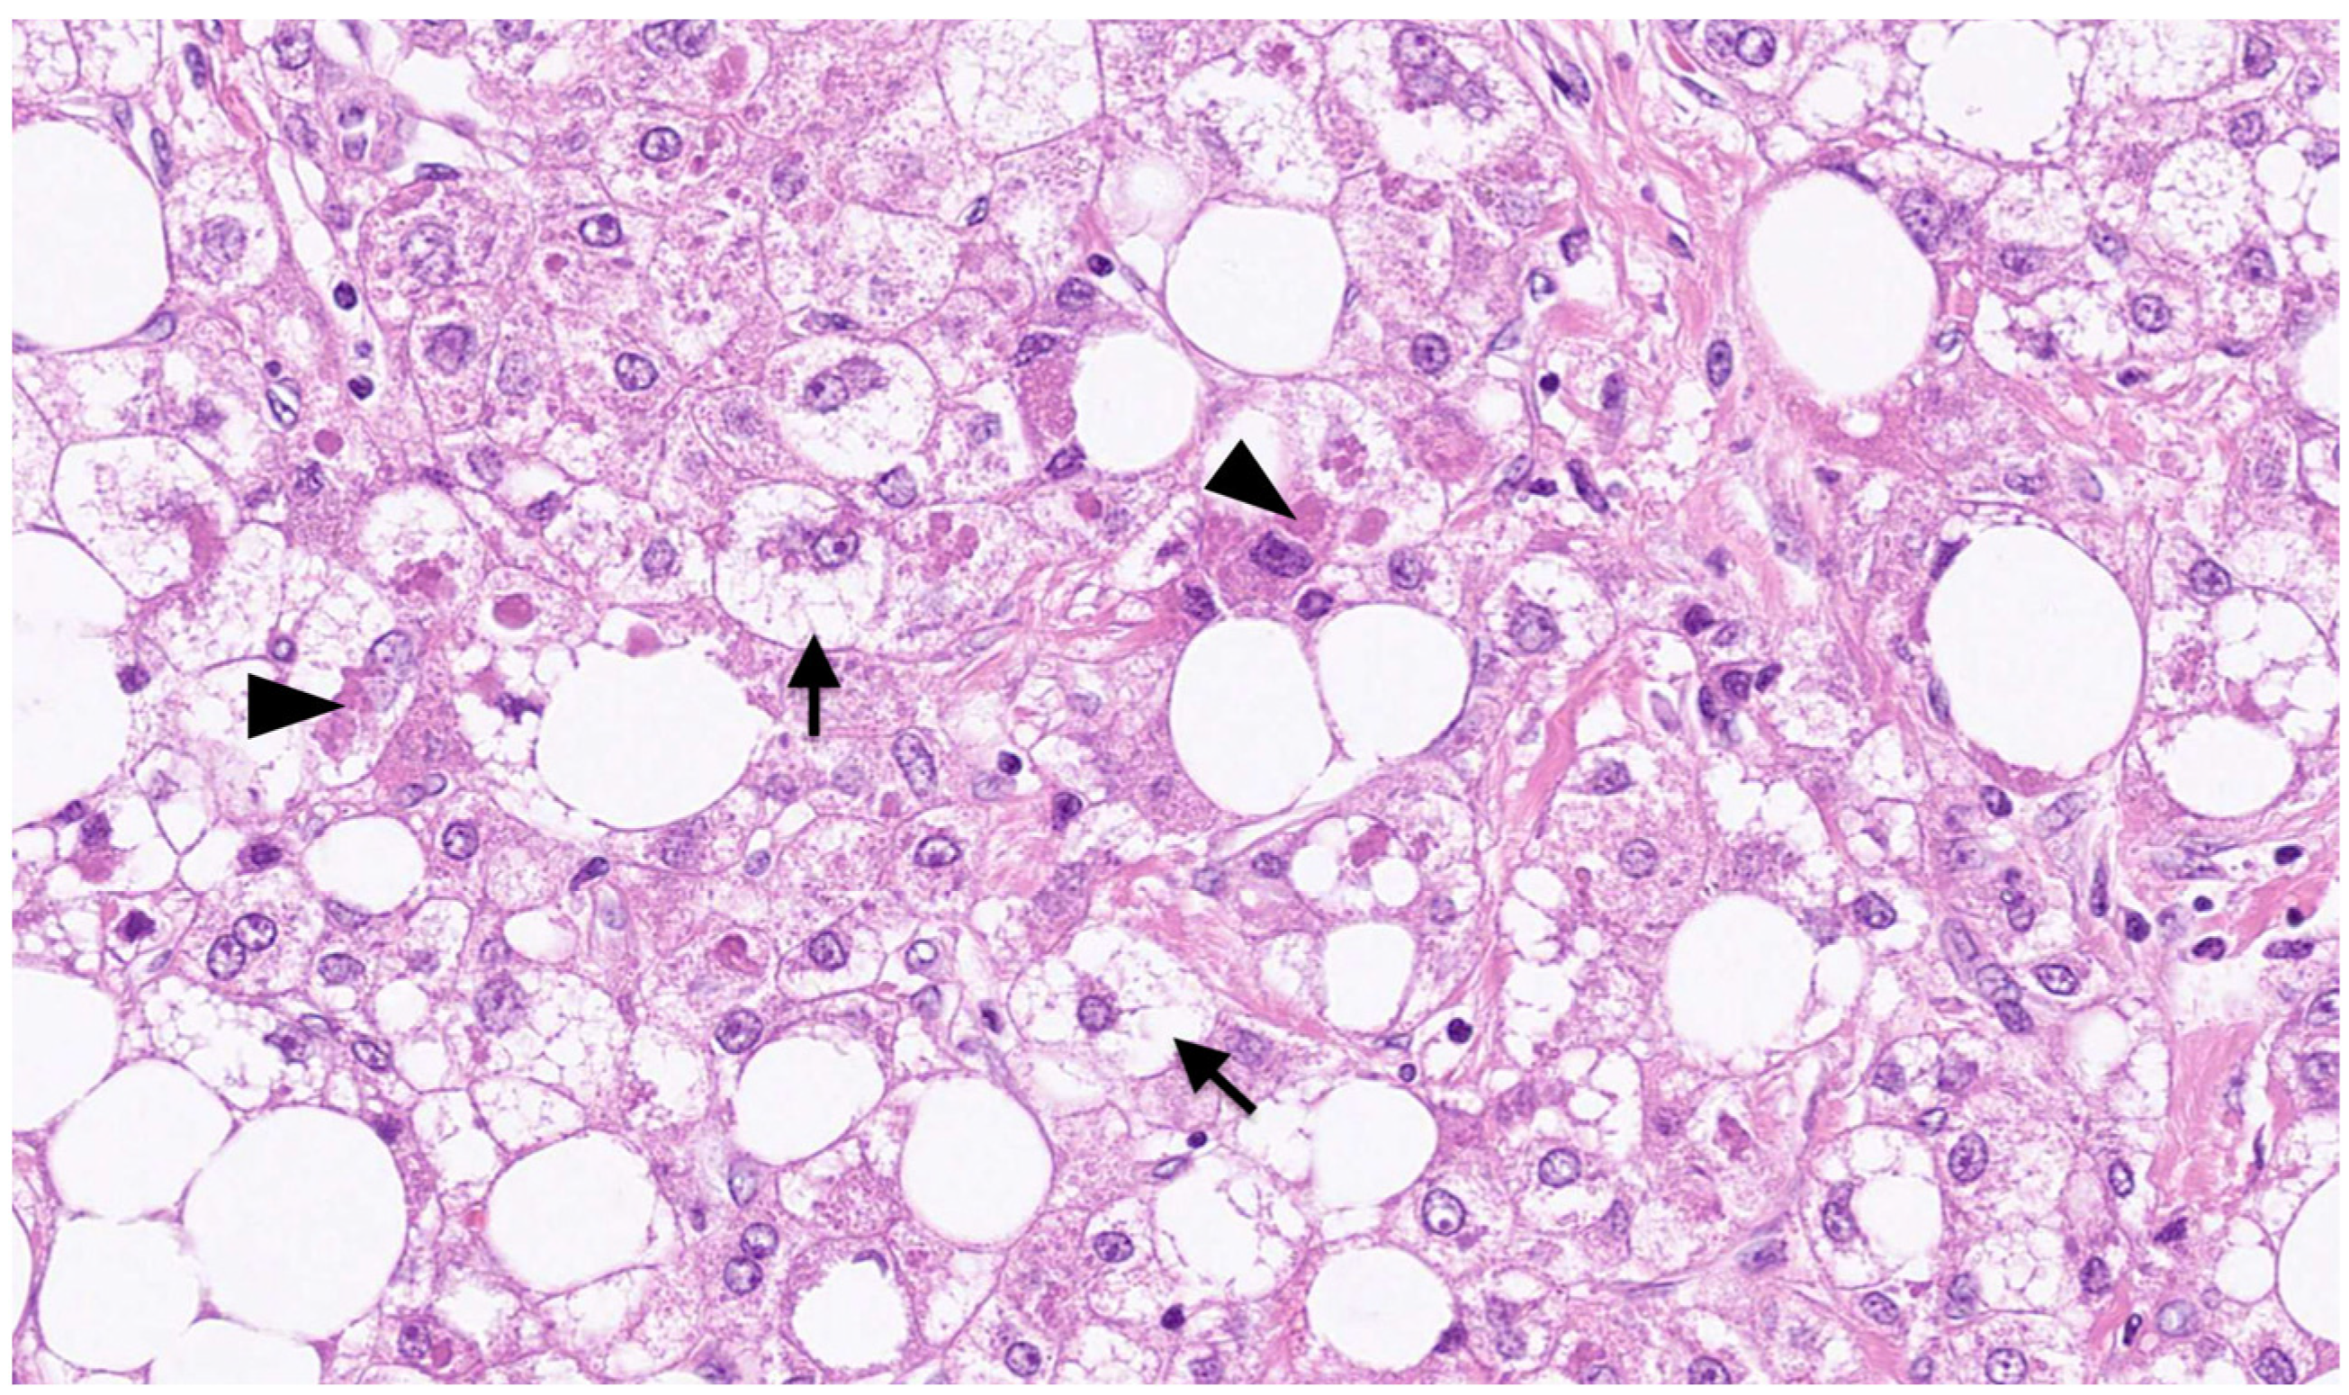

Figure 3.

Microscopic appearance of SH-HCC. Ballooning of malignant hepatocytes (arrows) and Mallory–Denk bodies (arrowheads) are observed in the tissue of HCC. This is an original photomicrograph with a magnification of ×260.

On macroscopic examination, SH-HCC is golden-yellow in color, reflecting steatosis, and is slightly firmer than conventional HCC, reflecting fibrosis [31] (Figure 1). The tumors are nodular and well demarcated, and the size ranges from 0.5 to 11 cm [15]. Microscopically, SH-HCC is characterized by large-droplet steatosis, inflammation, fibrosis, ballooning, and Mallory–Denk bodies, which are characteristic features of steatohepatitis (Figure 2 and Figure 3). The pattern of fibrosis is trabecular (thick bundles of fibrous tissue within the tumor) or pericellular (thin strands of fibrosis with a “chicken-wire” appearance) [30]. Although the diagnostic criteria for SH-HCC have not been established, at least 5% or 50% of the tumor area must show steatohepatitic features [15,30,31]. SH-HCC displays a less aggressive histological phenotype, lacking satellite nodules and microvascular invasion [34].